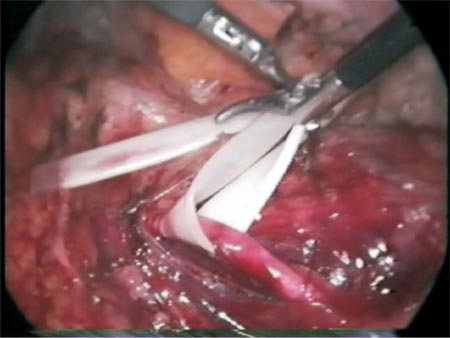

After the section of the stenosed area, the ureter spatulation (Photo 5) and the completion of the posterior wall anastomosis (Photo 6), the Levine catheter is disconnected from the ureteral catheter and a retrograde hydrophilic guidewire is inserted through the external orifice of the ureteral catheter which will be exposed by the left hand trocar (Photo 7 and Figure 5) with care in order to avoid the anastomosis posterior stitches to tear (during this manipulation if possible an atraumatic forceps should be maintained).

Photo 5 - Spatulation of the ureter.

Photo 6 - Constructing the posterior wall of the anastomosis.